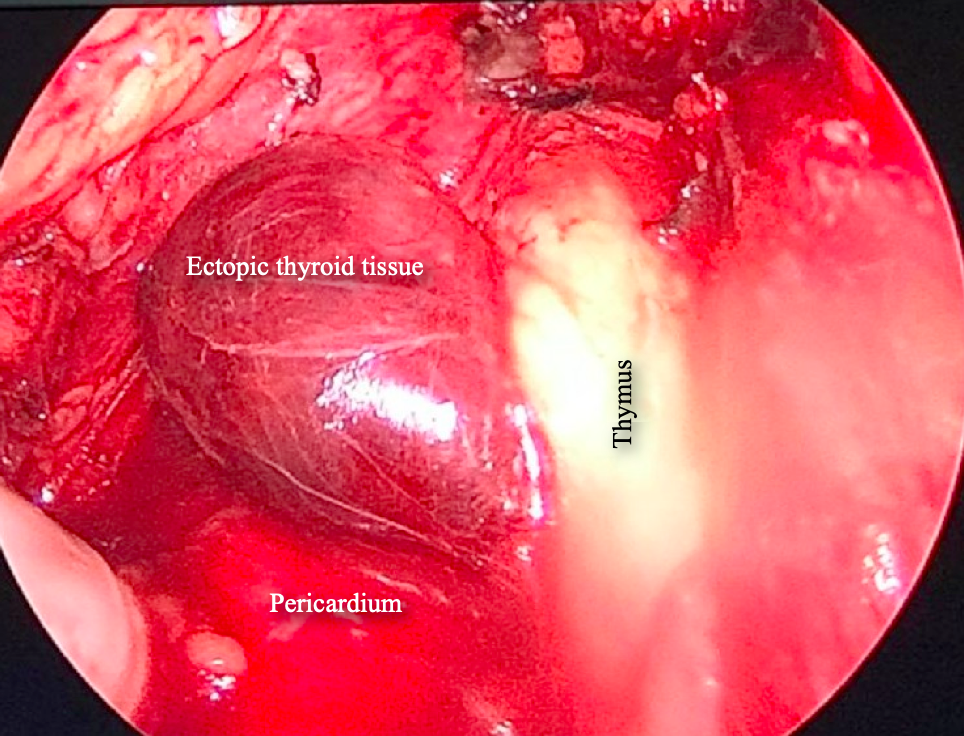

Figure, Ectopic thyroid] - StatPearls - NCBI Bookshelf Ectopic Thyroid - Endocrinesurgery.net.au Sites of ectopic thyroid localization along its descending pathway. | Download Scientific Diagram Ectopic thyroid tissue in the head and neck: a case series | BMC Research Notes | Full Text | Ectopic Thyroid